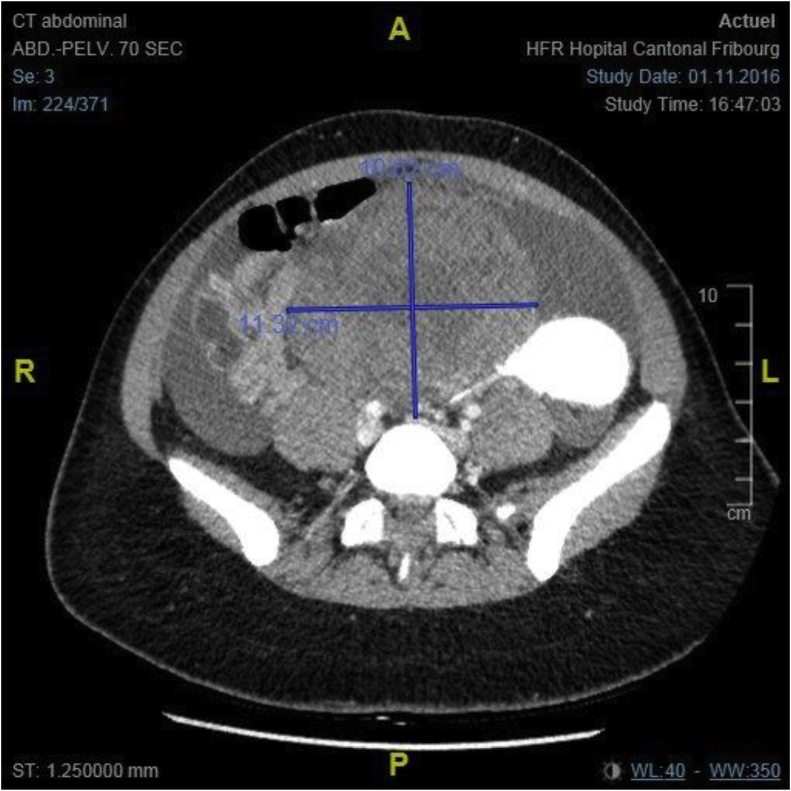

Fig. 2.

The CT Scan shows a voluminous pelvic mass of 98 × 112 × 125 mm attached to the uterus, with heterogenous enhancement and probably growing from the left ovary.